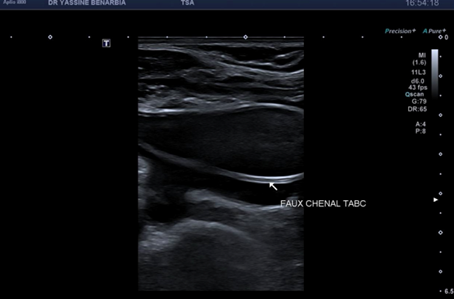

Du côté droit, l'examen met en évidence une dissection du tronc brachiocéphalique (TABC) avec présence d'un faux chenal circulant. Le flap intimal est clairement visible en mode B, séparant le vrai chenal du faux chenal. Au Doppler couleur, on observe un double flux avec des vélocités différenciées : le vrai chenal présente un flux rapide (codé en bleu qui s’éloigne de la sonde) tandis que le faux chenal montre un flux plus lent (codé en rouge qui se rapproche de la sonde).

Cette dissection s'étend à la carotide commune droite proximale. Le Doppler pulsé dans le vrai chenal montre un spectre triphasique conservé avec une vélocité maximale de 108,0 cm/s (normale) et un index de résistivité de 0,84 confirmant l'absence de retentissement hémodynamique. L'artère sous-clavière droite et l’artère vertébrale restent perméables avec des flux normaux au doppler.

Il s'agit donc d'une dissection stable du TABC et de la carotide commune droite proximale avec faux chenal circulant.